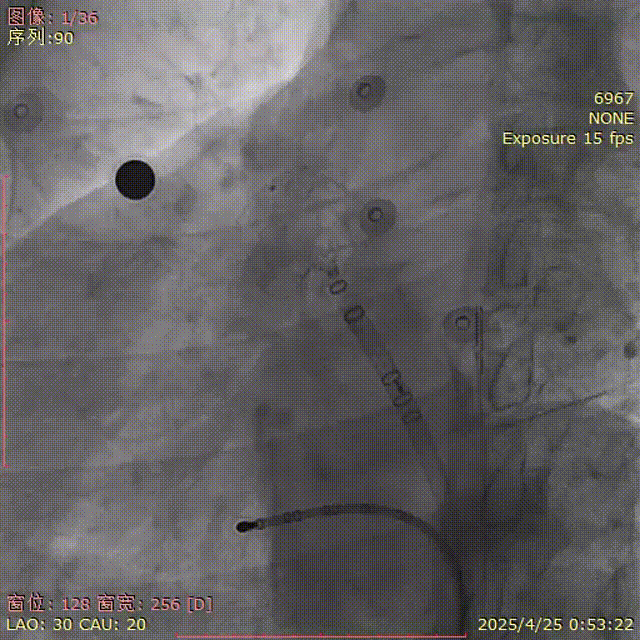

肝位造影

LAO 30° CAU 20°

牵拉后再造影

肝位及纯足位下缘轻微露肩(少于封堵器尺寸1/3),肩位下无明显露肩,评估符合PASS原则

LAO 30° CRA 20°

CAU 30°